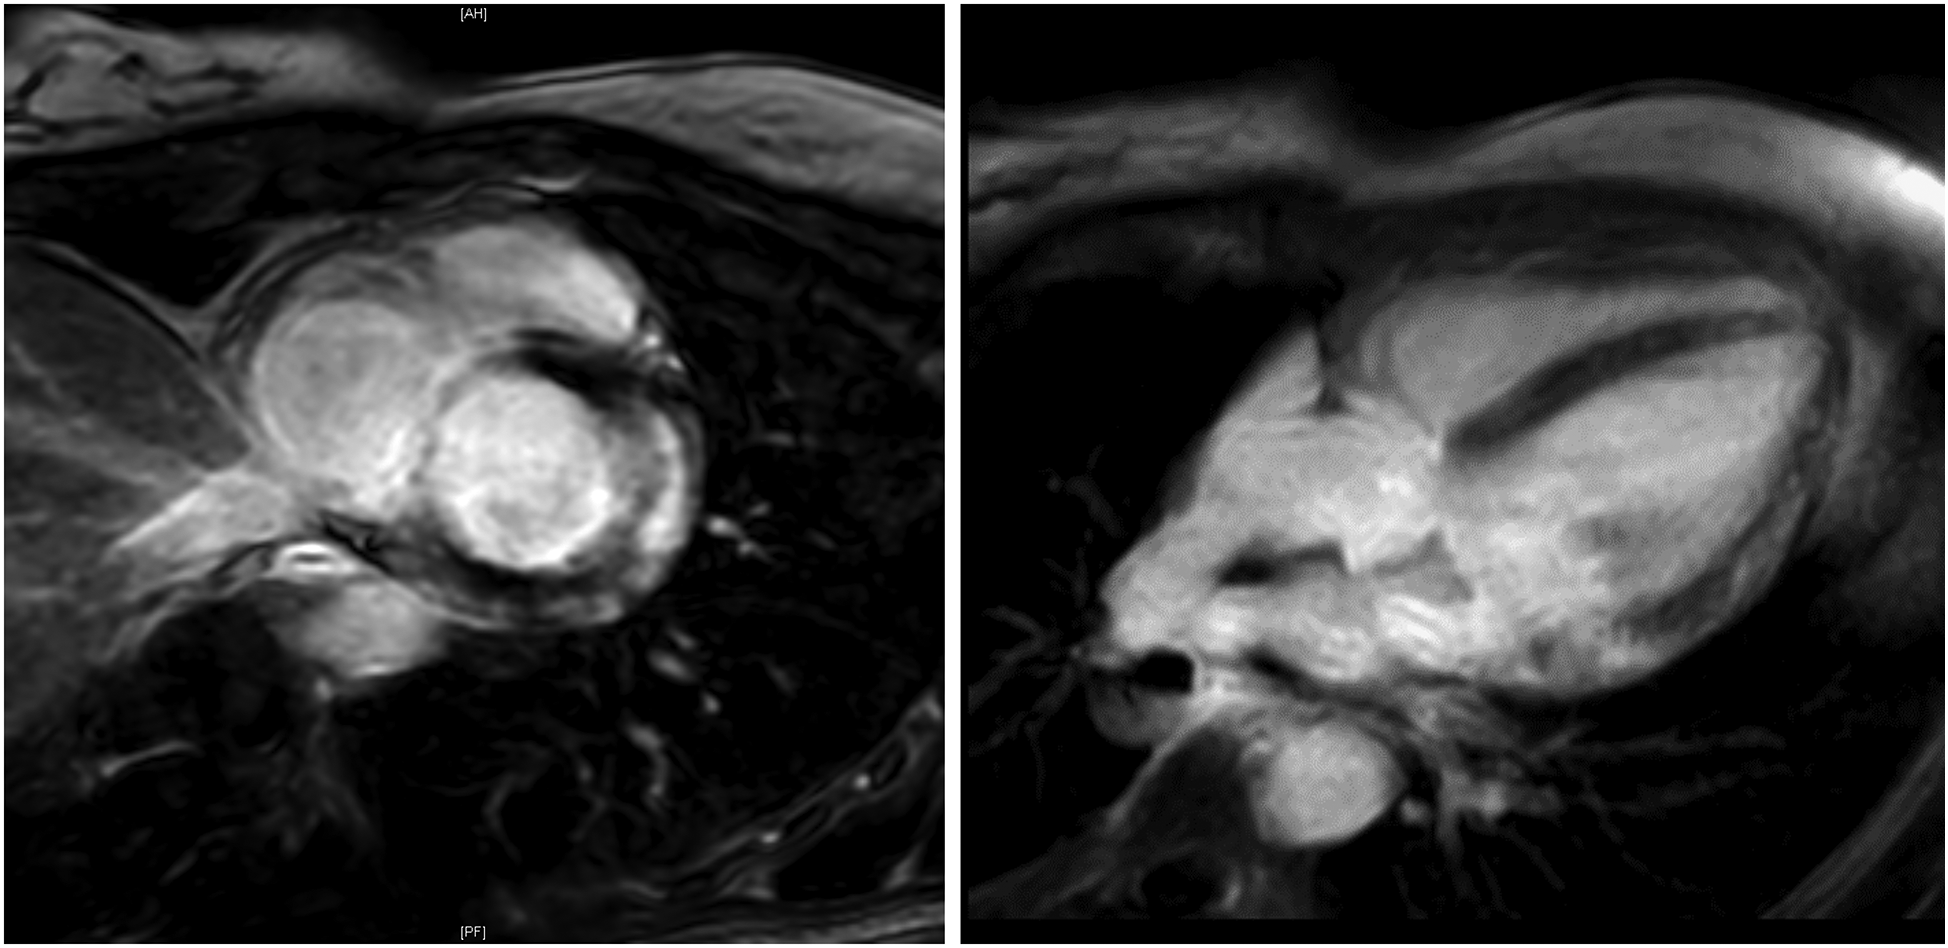

At stage I, ECG alterations were the main relevant finding (4/7, 57%). Three of them had significant T-negativity in ≥3 ECG leads (Figure 3), so the cardiac MRI as part of stage II was applied and lead to the diagnosis of myocarditis in one athlete (Figure 3) while the other 2 did not show any pathologies. The player with confirmed myocarditis was advised to take a break from sports practice, treated with nonsteroidal anti-inflammatory drugs and angiotensin-converting-enzyme inhibitors and controlled after 4–6 weeks and 3 months. One out of four athletes with pathological ECG showed a significant prolonged QT interval (QT 536 ms, QTc Bazett 513 ms; Figure 4). In combination with a positive family history for prolonged QT intervals, a congenital Long-QT-syndrome was diagnosed and consequently an exclusion from competitive sports was recommended. The cardiac MRI (stage II) in this player showed no relevant findings.

Figure 3

Cardiac MRI. Cardiac MRI of a young female ice-hockey player demonstrating late gadolinium enhancement of the lateral wall and global edema, following ECG-detected T-wave inversions, strongly suggesting myocarditis. MRI, magnetic resonance imaging.